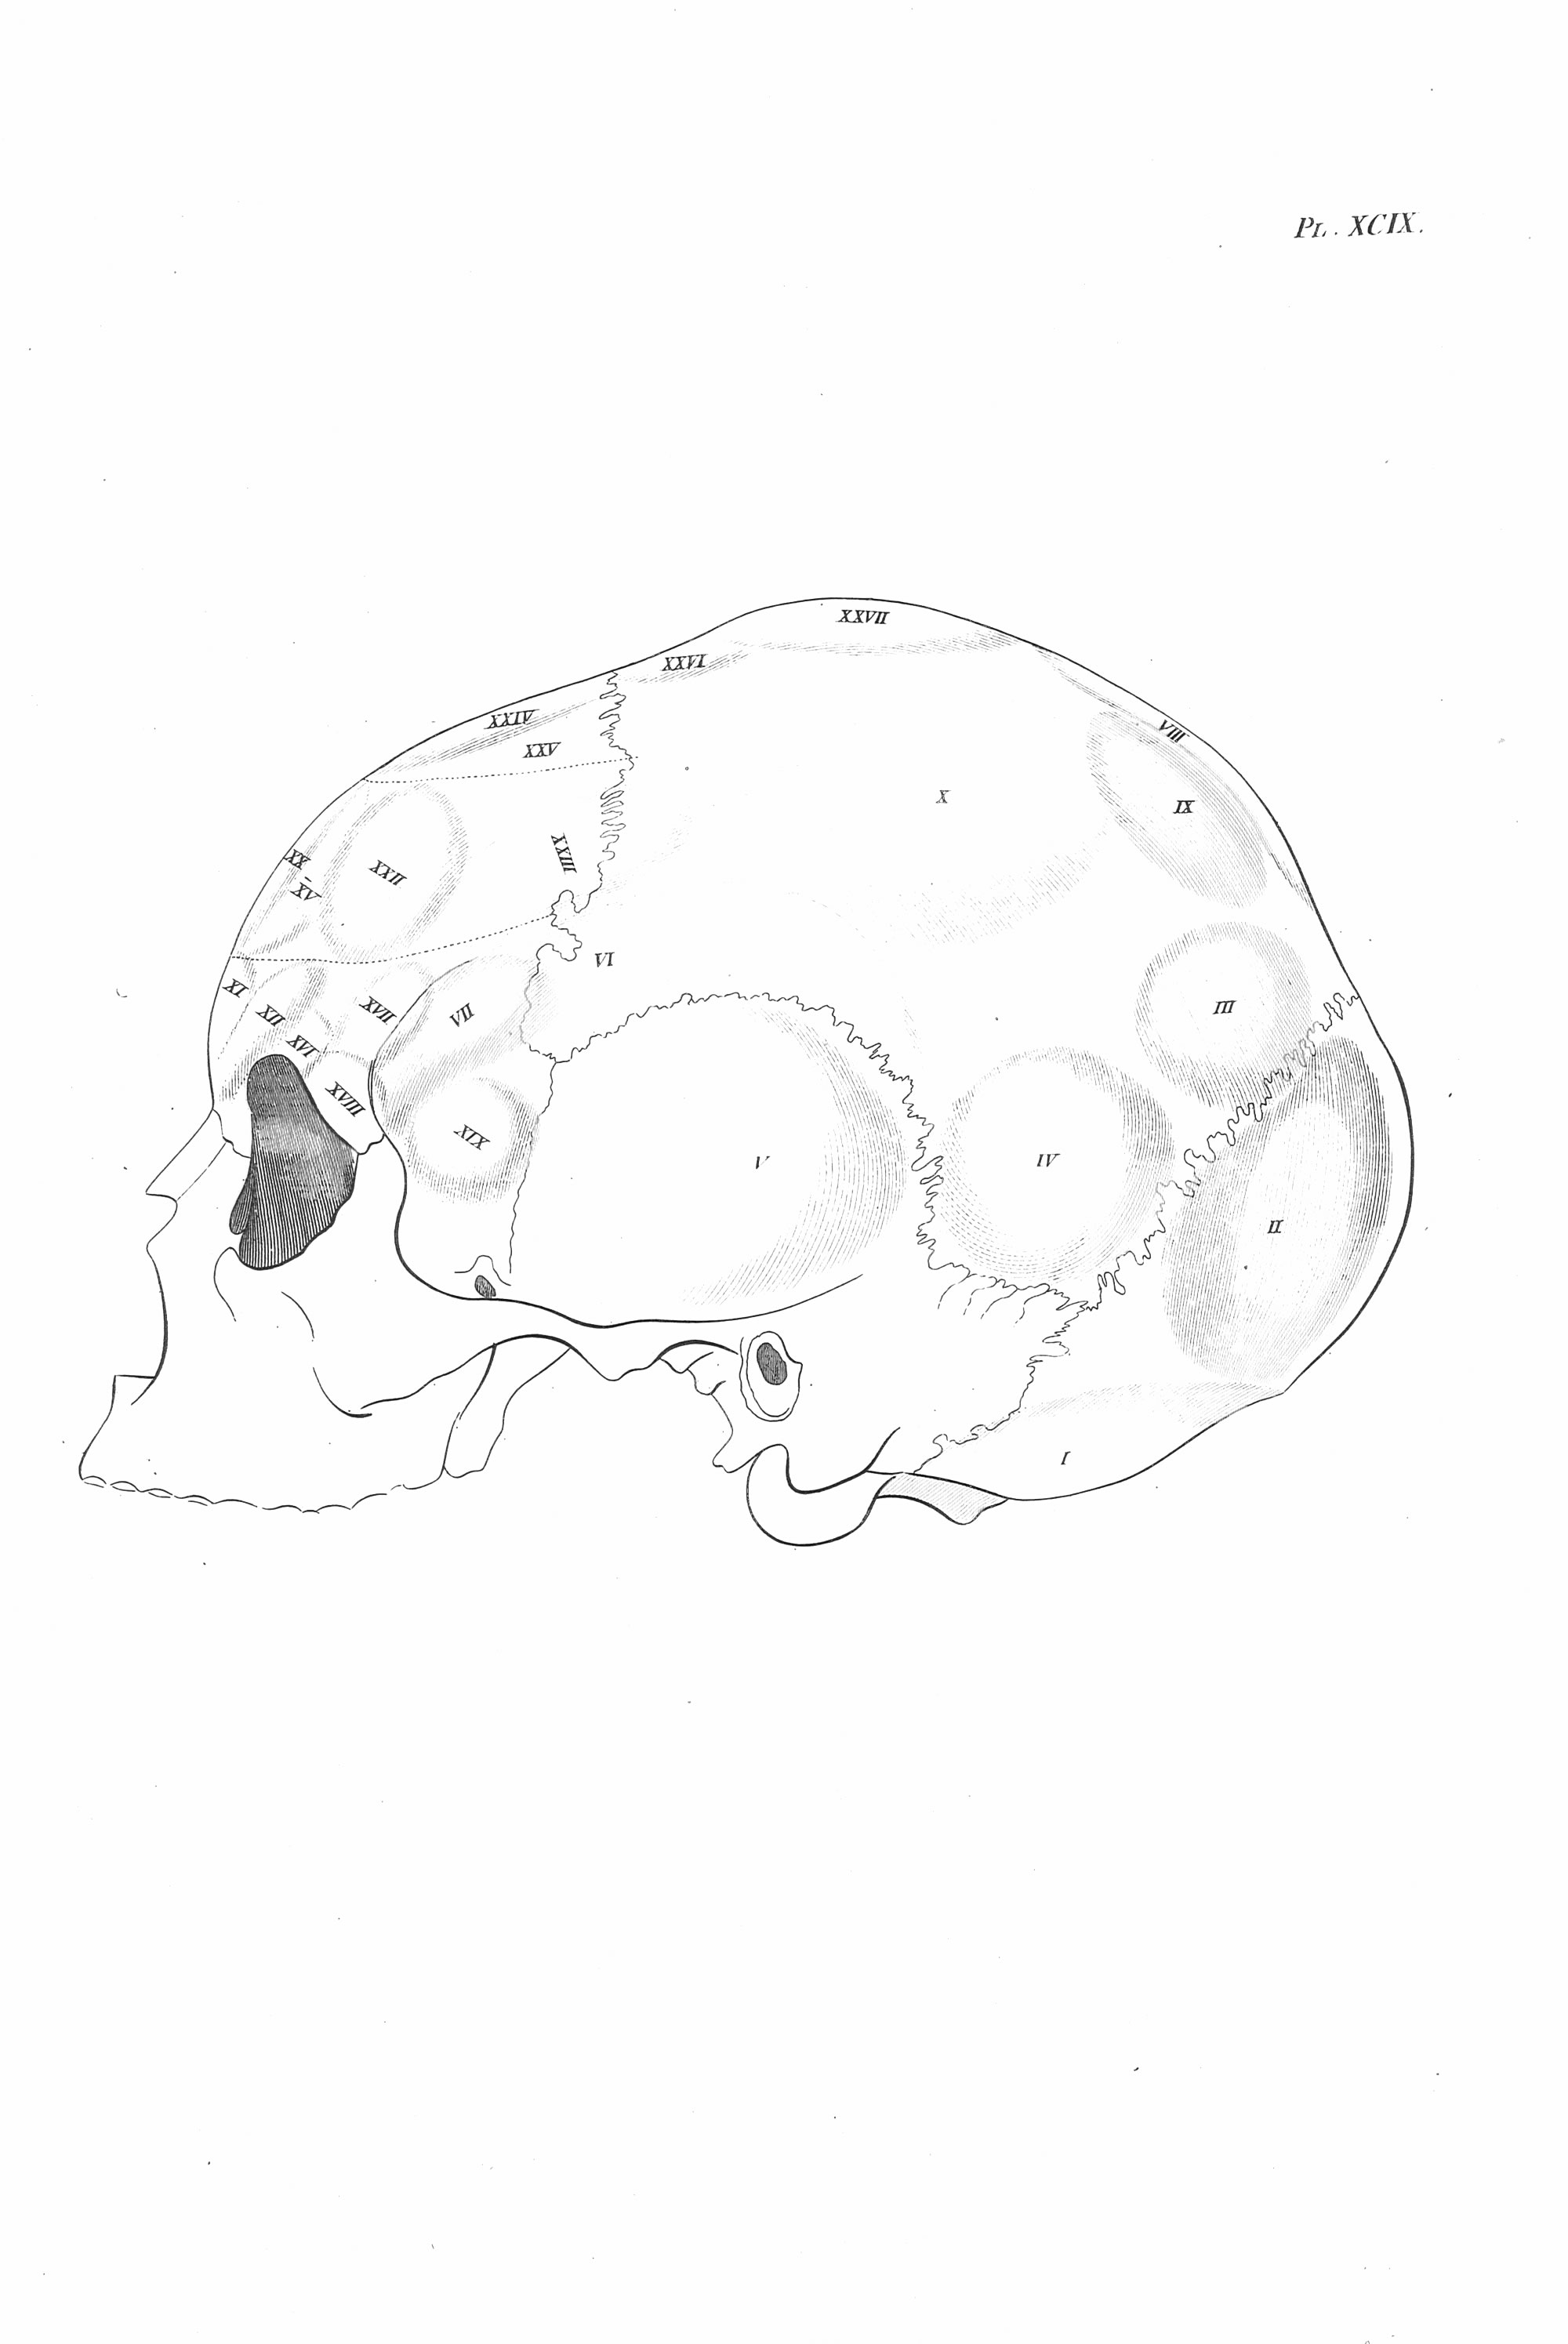

Gall, F. J. (1818). Anatomie et physiologie du système nerveux en général, et du cerveau en particulier, Avec des observations sur la possibilité de reconnoître plusieurs dispositions intellectuelles et morales de l´homme et des animaux, par la configuration de leurs têtes.

Librairie Grecque-Latine-Allemande, Vol. 3, I-XXXV u. 1-379 100 planches.